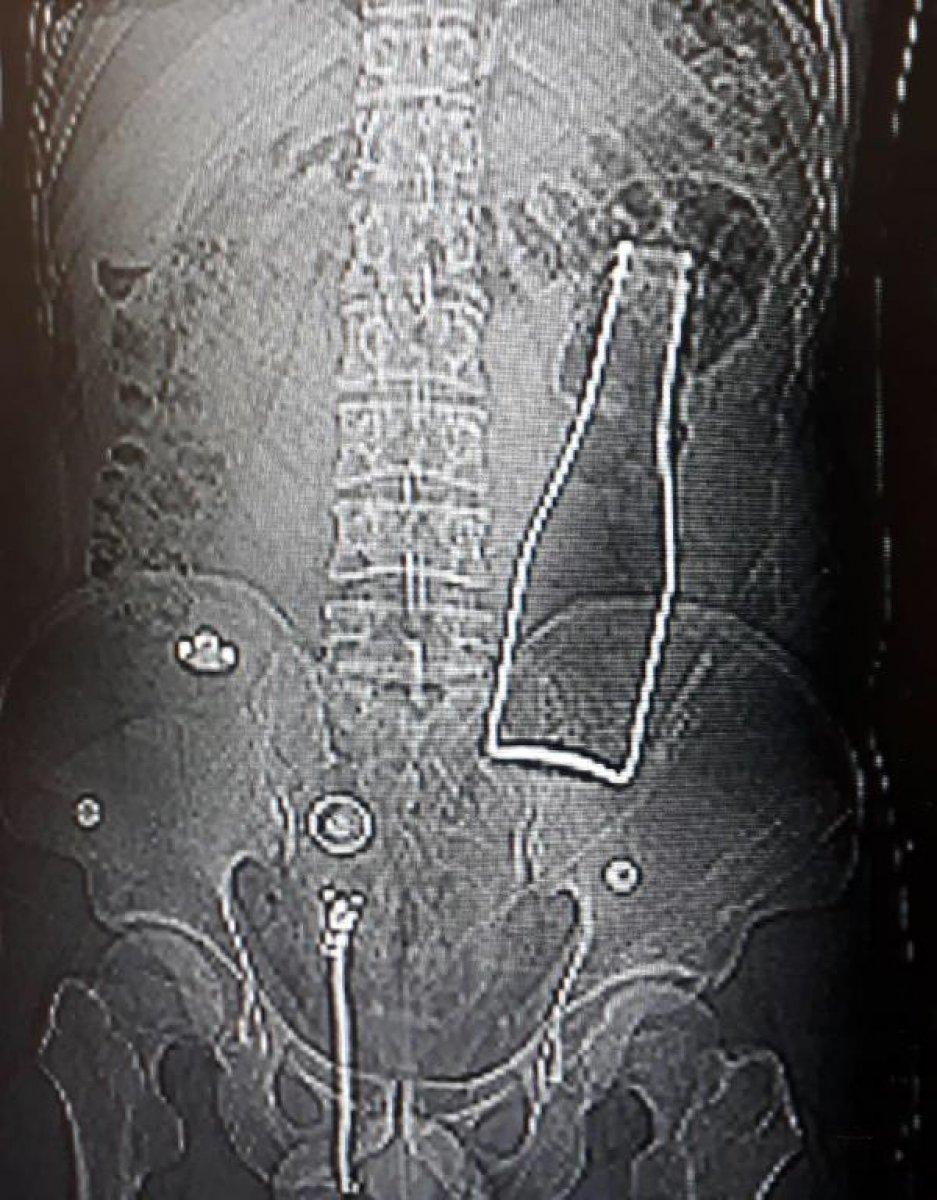

Karaman'da karın ağrısı şikayetiyle hastaneye giden Afganistan uyruklu A.E. adlı erkeğin, çekilen röntgen filminde beklenmedik bir durumla karşılaşıldı.

Röntgene yansıyanlara göre, A.E.'nin kalın bağırsağında şişe olduğu ortaya çıktı.

27 yaşındaki A.E.'nin makatından sokulduğu belirtilen soda şişesi, yaklaşık 1 saat süren ameliyatla alındı. A.E.'nin olayla ilgili verdiği ifade belli oldu.